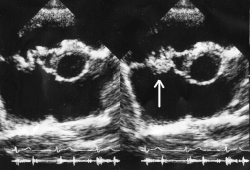

| Vegetação da válvula mitral causada por endocardite bacteriana | |

A infecção frequentemente produz vegetações, que são estruturas compostas de plaquetas, fibrina e microrganismos infecciosos. O aspecto da vegetação à ecocardiografia é de uma massa de material ecogênico, aderida a uma superfície endocárdica, geralmente anormal (valvas alteradas, locais de shunts, etc), e que apresenta uma mobilidade diferente da mobilidade da superfície à qual está aderida. Localiza-se geralmente na câmara para onde se dirige a regurgitação (face atrial na valva mitral e ventricular na valva aórtica) e tende a crescer nos folhetos das próteses biológicas e no anel das próteses mecânicas.[5] Nas valvas, ela pode se limitar às cúspides, mas pode invadir o anel ou as estruturas adjacentes, causando distúrbios de ritmo, comunicações entre as cavidades ou mesmo grandes abscessos. Ela pode acometer a valva mitral, a aórtica, a tricúspide ou a pulmonar e, com freqüência, lesando mais de uma. O acometimento pode ser por bactérias gram+, gram – ou por fungos.[6] Atualmente, alterações valvares degenerativas e próteses, e não mais a doença reumática, representam as causas mais comuns de endocardite em países desenvolvidos.[5]